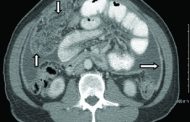

بلاحدود bilahodoud.ma على غرار دول العالم، تخلد وزارة الصحة والحماية الاجتماعية اليوم العالمي لمحاربة داء السل، الذي يُنظم هذه السنة تحت شعار: “السل يتجاوز الرئتين: لنعزز الوعي بالأشكال خارج... اقرأ المزيد